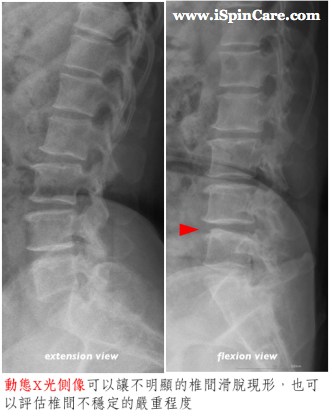

椎間滑脫並不一定造成脊椎的不穩定,必須比較彎腰和挺腰的動態腰椎側像,若兩者之間有明顯的差異,才能確定有脊椎的不穩定,這一點在治療建議上有著相當重要且決定性的影響。